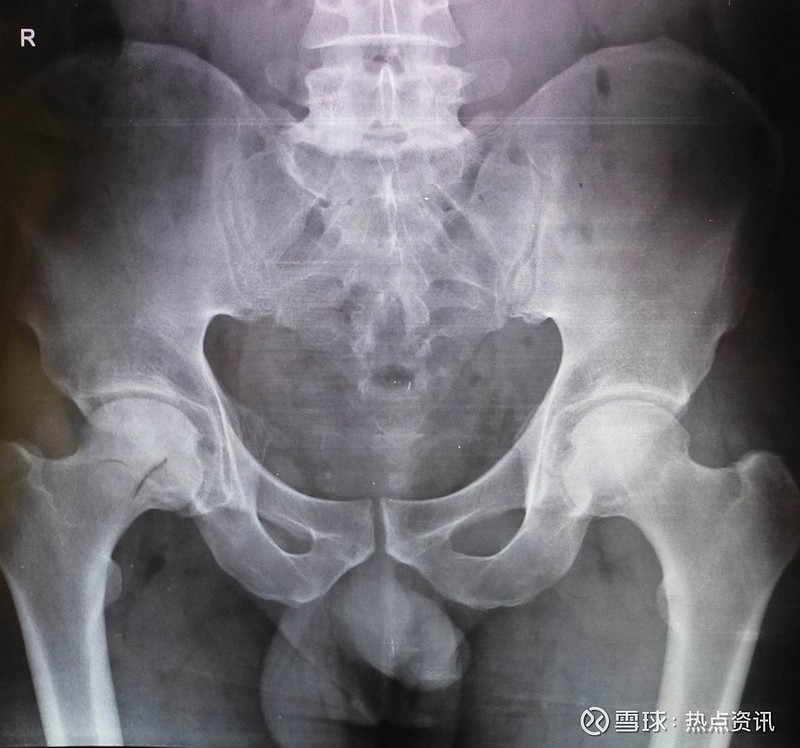

图2同一患者治疗8个月后,x线片显示右侧股骨头无菌坏死有新骨及骨小梁

股骨头缺血性坏死的检查方法——x光片